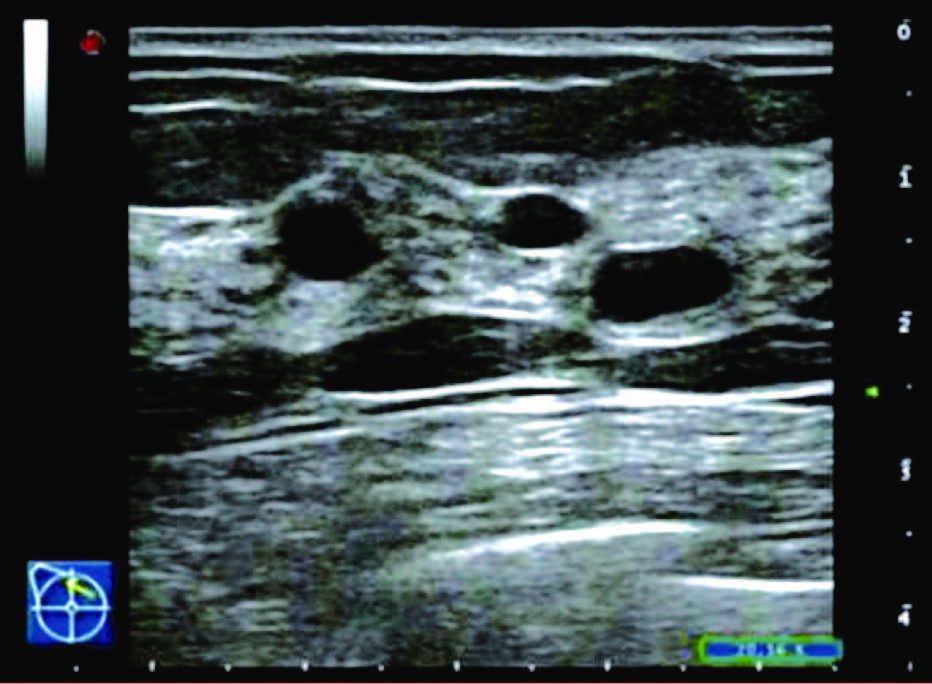

(3)囊性增生型:表现为乳腺组织回声增粗、增强,较杂乱,腺体内可见散在大小不等的圆形或椭圆形囊状无回声或长条形管状无回声区,边界清晰,壁薄光滑,透声好,内部偶见分隔回声带,也可有少许点状回声,内部无明显彩色血流信号。

患者,女,35岁,因双乳疼痛两月,乳头偶有针刺状疼痛,感到胸闷,呼吸不畅来院诊治。超声检查结果显示:右乳内可见多个无回声区,边界清晰,形态规则,其中3点方向较大一个1.7*0.6cm,内可见分隔光带,左乳内可见数个无回声区,边界清晰,形态规则,其中3点方向较大一个大小1.1*0.6cm内可见分隔光带,CDFI探查:未见异常血流信号显示。双侧乳腺切面形态轮廓正常,层次清楚。腺体厚薄不均,边界完整,欠规则,结构紊乱,分布不均,呈片状高回声区。